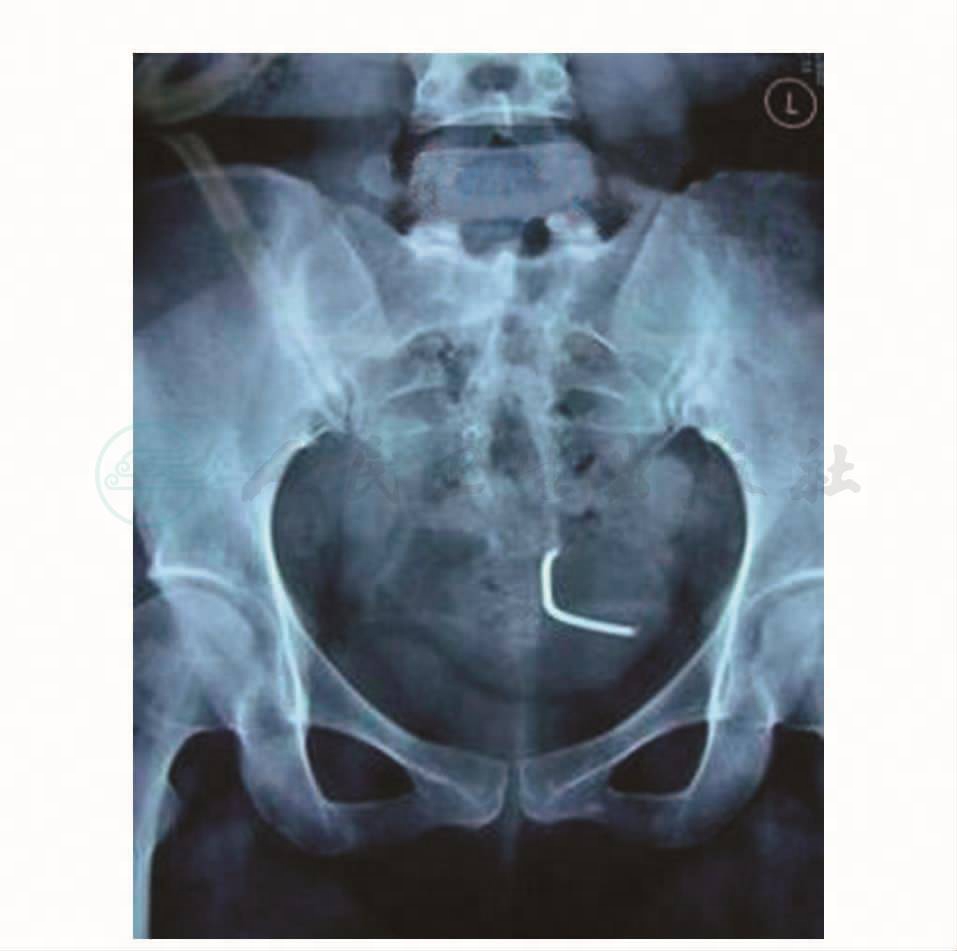

腹部X线检查:盆腔内见一条形金属影,距正中偏左2.5cm(图1)。

图1 腹部X线检查